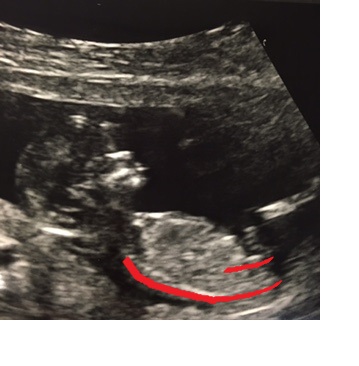

I'm also attaching the other pictures that I got the same day.